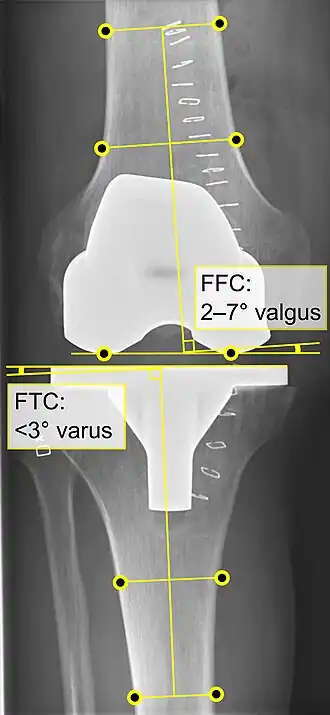

Knee replacement is routinely evaluated by X-ray, including the following measures:

- FFC: frontal femoral component angle. It is typically regarded as optimal when being 2–7° in valgus.[63]

- FTC: frontal tibial component angle, which is regarded as optimal when being at a right angle. A varus position of more than 3° has generally been found to increase the failure rate of the prosthesis.[63] -

- Anterior femoral notching (the femoral component causing reduced thickness of the distal femur anteriorly), seems to cause an increased risk of fractures when exceeding about 3 mm.[64]

- LTC: lateral (or sagittal) tibial component angle, which is ideally positioned so that the tibia is 0–7° flexed compared to at a right angle with the tibial plate.[63]